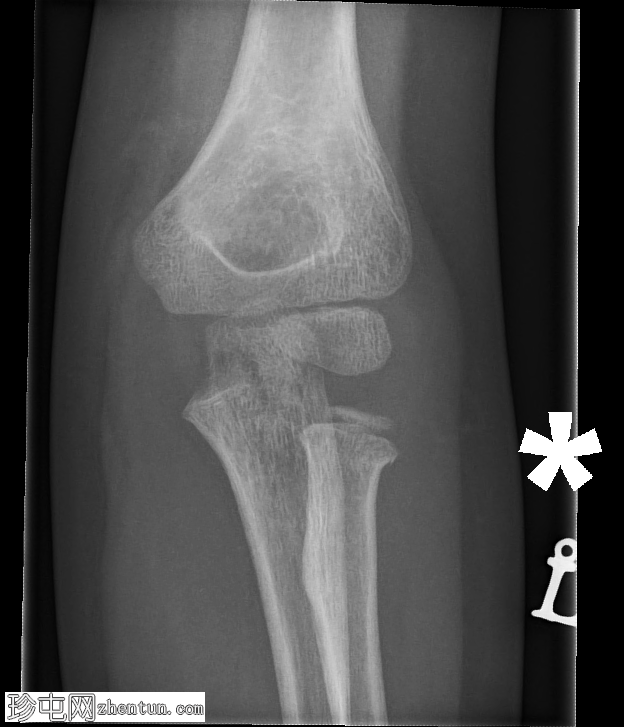

肘关节X线片

X线片

1.jpg

正位片

可见鹰嘴关节内骨折,桡骨颈轻度移位骨折,侧位片可见轻微硬化。肘关节对位良好。关节积液,表现为前后脂肪垫抬高。

儿科,桡骨颈骨折比桡骨头骨折更常见(与成人相反)。如本例所示,桡骨颈骨折通常表现隐匿,轻微硬化或轻度成角可能是唯一的体征。

鹰嘴骨折虽然不常见,但容易被忽略,因此是常见的漏诊骨折。侧位片通常最有帮助。

务必始终评估关节对位情况。如果存在桡骨小头关节脱位,则该损伤属于蒙特吉亚骨折脱位。描述关节对位正常非常重要。